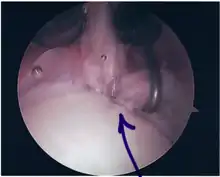

Following inspection and determination of the extent of injury, the basic labrum repair is as follows.

- The glenoid and labrum are roughened to increase contact surface area and promote re-growth.

- Locations for the bone anchors are selected based on number and severity of tear. A severe tear involving both SLAP and Bankart lesions may require seven anchors. Simple tears may only require one.

- The glenoid is drilled for the anchor implantation.

- Anchors are inserted in the glenoid.

- The suture component of the implant is tied through the labrum and knotted such that the labrum is in tight contact with the glenoid surface.